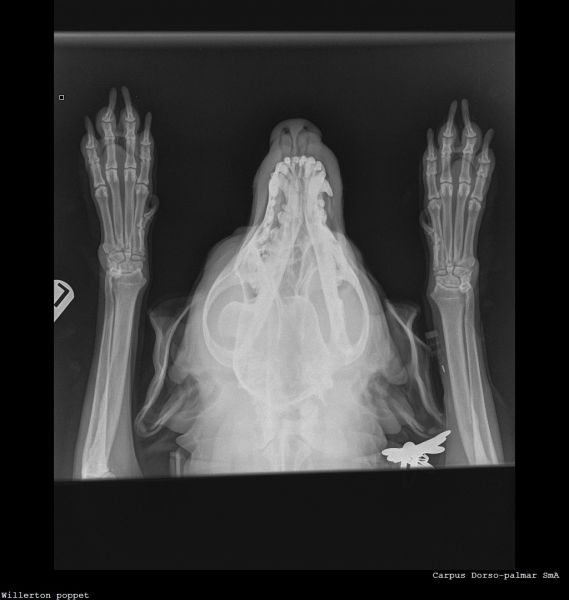

Hi vets, Wondered if anyone could give a second opinion on these X-rays? 12 year old dog. Left forelimb lameness improved with antibiotics then got worse again. Gradually worsening over the past 3 months. Pain on palpation around the left wrist joint and has been treated for an infected claw on the left paw 8 weeks ago (the starting incident for vet treatment). Muscle loss around left shoulder and now winging from the elbow. My first practitioner vets have sent it off for an orthopaedic consult but in the meantime it would be nice to settle my brain that nothing terrible is happening with my dog 🤞🏻 Thank you 🙏🏻Willerton_poppet_CARPUS-Carpus Dorso-palmaWillerton_poppet_SHOULDER-Shoulder Lateral(1)Willerton_poppet_SHOULDER-Shoulder Lateral

Hello and thank you for this interesting question.  With my harsh scientific hat on rather than my people-hat, I can point out that nobody can tell you even from a very comprehensive series of x-rays that nothing terrible is happening with your dog; however, investigation of any areas of concern is always a good way forward. We do not read radiographs as part of this series; I have no additional qualifications in reading radiographs so this is best done by the vet who has the full context available to them and if they are unsure, then an expert.  Sometimes if experts are unsure, they will offer further tests or a biopsy.  My job is to help you to get the best out of your vet and I, perhaps like your vet, am a little concerned about the way some of these joints present on the radiograph.  It therefore seems a good idea to maximise the effectiveness of the radiographs already taken, to ask for the comment of an expert.  This seems a reasonable and appropriate next step. Lameness is usually a reflection of pain; the fact that an animal is lame tends to imply that it hurts to put the leg down properly.  The changes to the nail may have been part of a cause of this (for example, fungal infection affecting bone causing pain,  not the only possibility) or part of a consequence of this (ie lameness / altered weight-bearing causing damage to the nail).     It  may be worth asking whether your pet can have pain relief in the meantime, in order to make them more comfortable.  Wishing you the best of luck with this case going forward; please would you let us know how your chihuahua gets on?